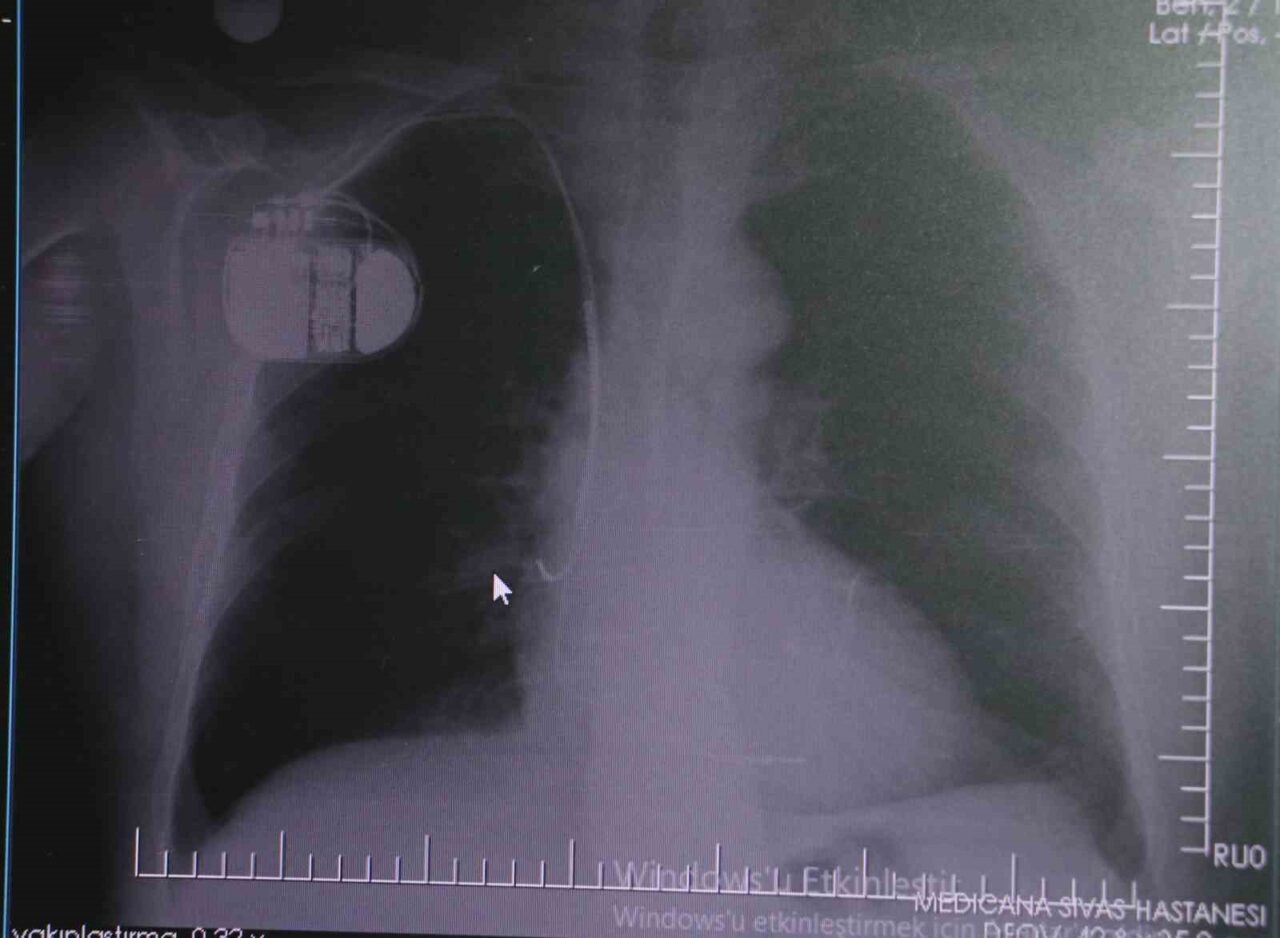

Dr. İsmail Erdoğu, kalp pillerinin önemine dikkat çekerek, yeni nesil kalp pillerinin MR cihazları ile uyumlu çalıştığını, ancak yine de tarama cihazlarından geçilmesinin önerilmediğini belirtti. Soğuk nedeniyle vücutta oluşan titremelerin, kalp pilinin yanılmasına yol açabileceğini ve bu durumun istenmeyen şoklamalara neden olabileceğini ifade etti. “Bu nedenle hastalarımızın soğuk havalarda daha fazla dikkat göstermelerini bekliyoruz” dedi.

Kalp pillerinin MR cihazlarında kullanılabildiğini hatırlatan Dr. Erdoğu, bu durumun önemli bir cerrahi önemi bulunduğunu ve kalp pilinin, tıp alanındaki son 30 yılın en büyük yeniliklerinden biri olduğunu dile getirdi. Kalp pilleri, hastaların yaşama mücadelesinde önemli bir rol oynamakta. “Bir defibrilatör olmadan hastanın ritmini düzeltmek mümkün değil. Kalp pili, hastanın durumunu algılayarak gereksinim duyulduğunda devreye giriyor ve hastayı hayata döndürebiliyor. Ancak soğuk hava, kalp pilinin hafızasında karışıklığa neden olabilir. Bu durumu önlemek için, kalp pili bulunan kişilerin kış aylarında ekstra dikkatli olmalarını öneriyoruz” diye açıkladı.